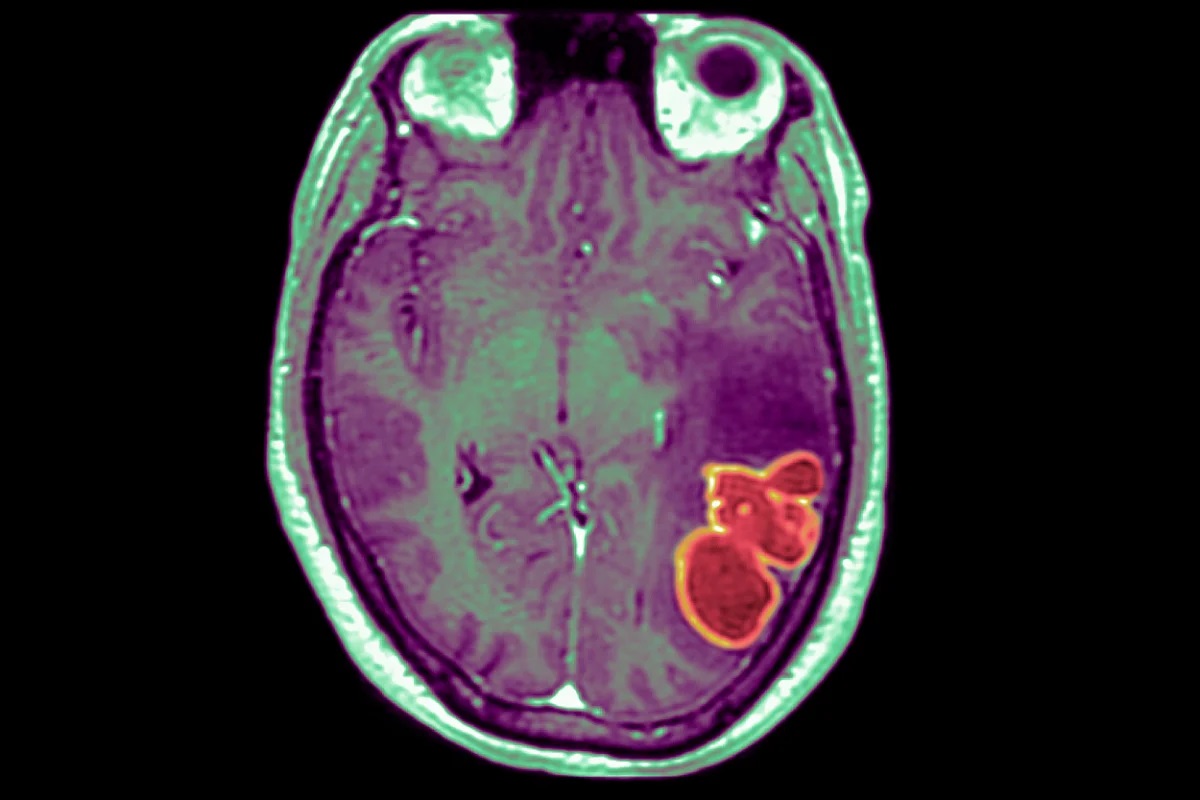

Oficialii din domeniul sănătății investighează un număr tot mai mare de abcese cerebrale la copii, observate pentru prima dată în Las Vegas, dar care au început să apară și în alte părți ale țării, relatează Daily Caller.

În această perioadă, numărul de abcese cerebrale la copii s-a triplat în Nevada, crescând de la o medie de patru-cinci pe an la 18, a relatat postul. Fiind singurul medic care tratează aceste cazuri în statul Nevada, Bragg a luat act de această creștere neobișnuită și a anunțat autoritățile de sănătate publică.

Bragg a dezvăluit că toate cazurile au început în mod similar, pornind de la o afecțiune comună, cum ar fi o durere de urechi sau o infecție a sinusurilor. În decurs de o săptămână, însă, era evident că acei copii sufereau de ceva mai grav.

Sood crede că boala covid-19 a dislocat temporar alte infecții. Acum, când cazurile de covid-19 au început să scadă, alte boli au revenit „în forță”, ceea ce ar putea explica creșterea numărului de infecții cerebrale. Deoarece abcesele cerebrale sunt de obicei cauzate de un procent foarte mic de infecții ale sinusurilor și de infecții ale urechii interne la copii, creșterea acestor infecții ar crește în mod logic numărul de infecții cerebrale observate, a motivat Sood.